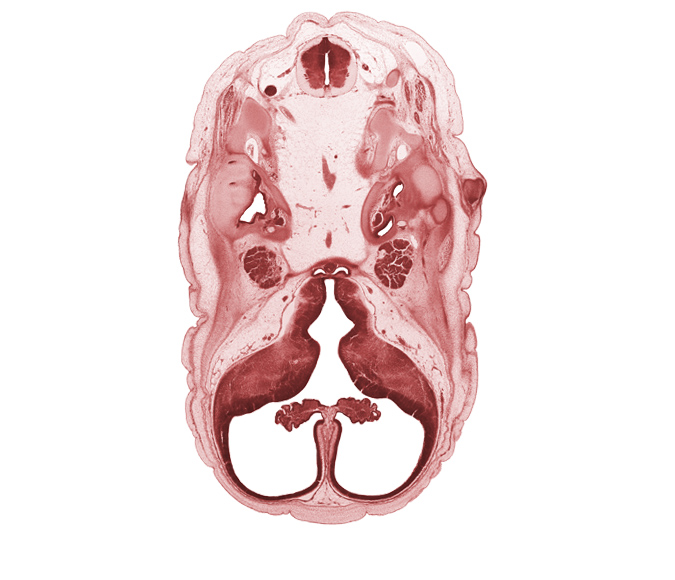

Carnegie Embryo #4090 | Location: 8-11

Keywords: C-1 spinal nerve, abducens nerve (CN VI), basilar artery, central canal, cerebral vesicle (hemisphere), choroid plexus, cochlear duct, facial nerve (CN VII), falx cerebri region, head mesenchyme, hypoglossal nerve (CN XII), interventricular foramen, junction of basilar artery and vertebral arteries, lateral ventricle, lateral ventricular eminence (telencephalon), medial ventricular eminence (diencephalon), neurohypophysis, otic capsule cartilage, pharyngeal arch 1 cartilage (Meckel), posterior communicating artery, subarachnoid space, trigeminal ganglion (CN V), utricle, venous plexus(es), vertebral artery

Source: The Virtual Human Embryo.